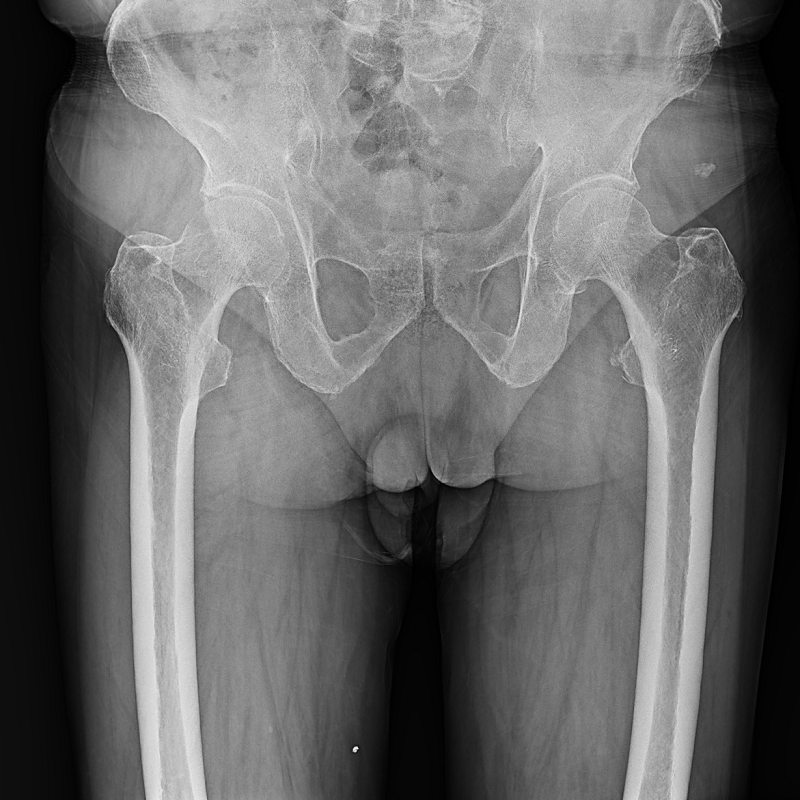

●呈現(xiàn)全下肢或全脊柱圖像

●在脊柱及下肢畸形矯正手術(shù)治療中,為術(shù)前方案制定和術(shù)后復(fù)查提供精準(zhǔn)測(cè)量

●有效解決傳統(tǒng)X光片不能一次成像問題,為患者提供更加優(yōu)質(zhì)的醫(yī)療服務(wù)

點(diǎn)片裝置可實(shí)現(xiàn)大范圍縱向移動(dòng),高效完成各部位、全身拼接等檢查需求